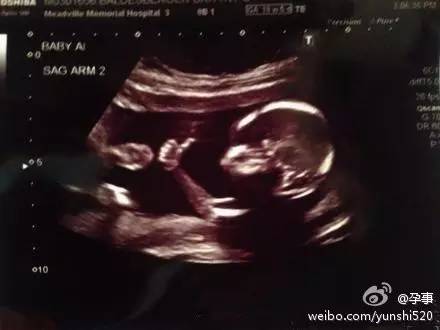

孕16周的胎宝宝↑↑↑,完美的全身照

告诉你一个小秘密,如果你想保留一张宝宝的全身B超照,要注意选择时间。早于15周,画面里宝宝太小;大于16周,画面里又放不下宝宝。所以最好选在15~16周。